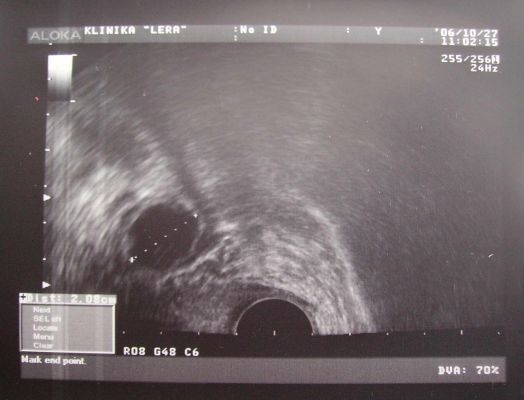

На данном этапе осуществляется ультразвуковое исследование для выявления момента овуляции. После окончания менструации специалист проводит наблюдение за процессом созревания фолликулов и выходом яйцеклетки каждые 2-3 дня. На ультразвуковом исследовании также можно увидеть желтое тело.

Созревание фолликула в яичниках – это сложный биологический процесс, который занимает около 14 дней при 28-дневном цикле. В течение этого времени активно вырабатываются эстрогены, способствующие росту и созреванию яйцеклетки. На завершающем этапе созревания фолликул достигает диаметра 2 см. Под воздействием лютеинизирующего гормона и увеличивающегося давления фолликулярной жидкости происходит разрыв стенки фолликула, и зрелая яйцеклетка вместе с окружающей жидкостью выходит наружу – это и есть овуляция.

На второй неделе цикла, в период с 8 по 10 день, при проведении процедуры ЭКО осуществляется ультразвуковое обследование (фолликулометрия). Это исследование позволяет выявить наличие и количество доминирующих фолликулов, а также оценить их развитие. Когда фолликулы достигают необходимых размеров, женщине вводят препарат ХГЧ, который стимулирует их созревание и подготавливает к пункции. Овуляция, как правило, происходит через 40-48 часов после введения ХГЧ, поэтому пункция созревших фолликулов осуществляется до её начала, обычно через 35-36 часов после инъекции. Для успешного прохождения протокола ЭКО крайне важно следовать всем рекомендациям врача, и это касается не только женщины, но и будущего отца.